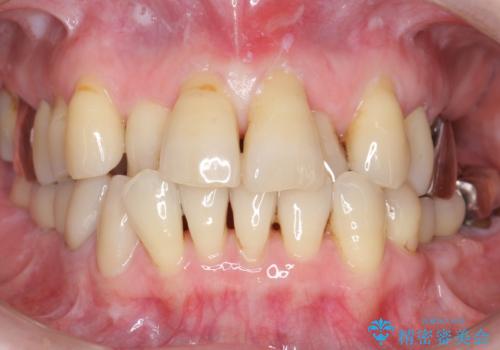

気にされていた歯の動揺や違和感がなくなり、喜んで頂けました。

モチベーションがあがり、大臼歯欠損部位の治療に関しても前向きに検討して下さるとの事でした。

セラミック治療の注意事項(リスク・副作用など)

- 天然歯を削ります

- 硬い素材は天然歯を傷つけてしまう場合があります

- かみ合わせや歯ぎしりが強すぎる方はセラミックが割れてしまう可能性があります